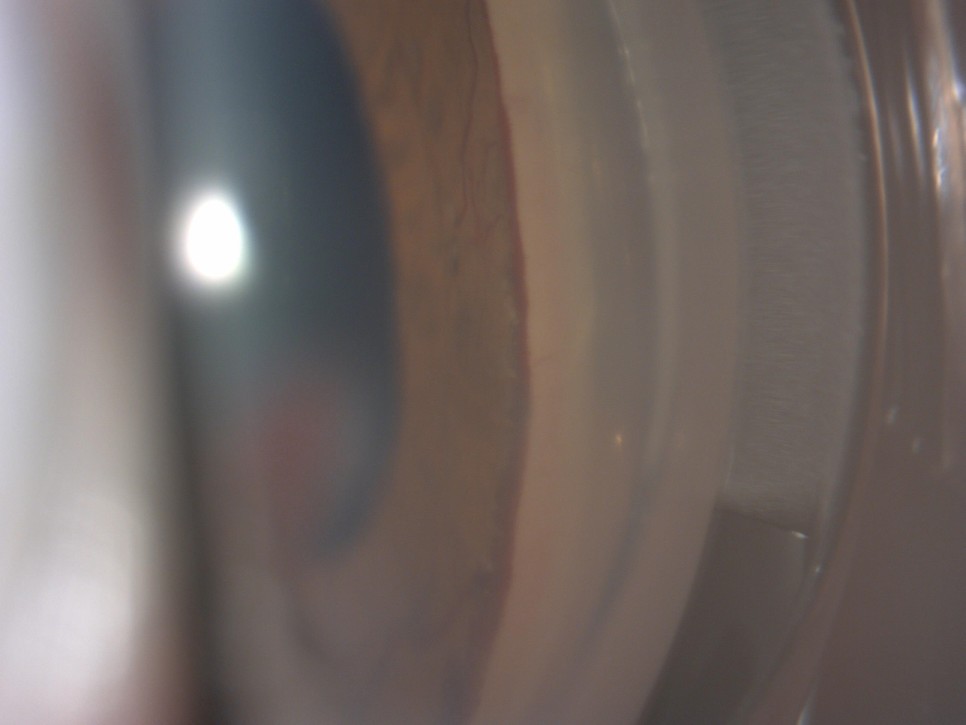

2 . Gonio photography

신생혈관이 방수 유출로인 섬유주를 덮음으로써 발생하는 전방각의 유착을 확인하기 위하여 Goniophotography로 촬영한 사진이다.